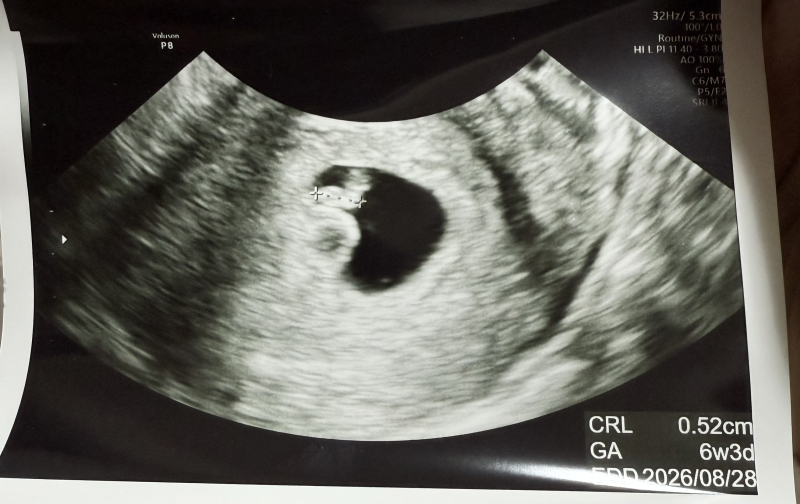

胎嚢の中に赤ちゃんとは別の膜状のものが見えます、

6w6の時に6w3に相当する大きさの胎芽と心拍が確認できました。排卵日がずれていたので、このずれはあまり気にしていませんが、10日ほど前に胎嚢と卵黄嚢のみの確認の際に見えていなかった、膜に包まれた空間?も一緒に確認されました。血流はないようなのでふたごの可能性は低いです、

これはなんでしょうか。危ないものでしょうか。

胎嚢の中に、赤ちゃんとは別の何かが見えることがご心配なのですね。

実際にエコーを拝見していませんので、なかなかお写真からですとはっきりとしたことは明言できませんが、双子ではないということですと、もしかすると卵黄嚢が見え方によって濃く見えているのかもしれません。

健診時に特に医師から何も指摘がなかったのであれば、少なくとも異常なものではないと思いますので、また健診時にもご確認なさってみてくださいね。